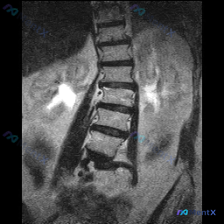

今天看到一个很有意思的案例,很能体现影像阅片里的「思维陷阱」,整理出来和大家一起理一理思路。 --- 先看「初始诉求」与「影像事实」的冲突 用户明确问的是「脾脏病变」,但点开图像发现——这根本不是上腹部的图像,而是一张 胸腰段脊柱区域的 MRI T2 加权冠状位。 这是第一个关键点:不能被临床申请单...

网上看到一份影像资料,申请原因写的是排查“Scoliosis(脊柱侧弯)”,拍的是腰椎MRI T2加权冠状位。 先不说侧弯,影像里有几个点先放出来: 1. 脊柱序列其实挺规整,椎间隙也对称,没看到明确的侧向成角畸形 2. 但两侧腰大肌区域里有明显的圆形/类圆形高信号囊性灶 3. 右侧病灶还和肾脏结构...

整理到一份腰椎MRI的影像分析资料,第一眼看到的是很明确的脊柱问题: - 腰椎向右侧凸,凹侧在左 - 多节段椎间盘T2信号减低,凹侧椎间隙更窄 - 椎体边缘有骨赘形成 但再往下看,影像里还提到了一个脊柱外的意外发现,而且风险等级可能比脊柱侧凸更高… 想先问问大家:如果是你拿到这份只有冠状位的腰椎MR...